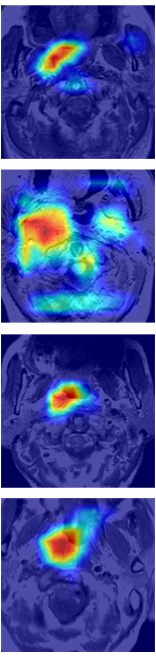

Some examples of spatial attention coefficients are shown in Figure 11. We can see that, several locations may fire at the beginning of training phase and then energy will slowly build up over ROIs and reduce the attention to false positives.